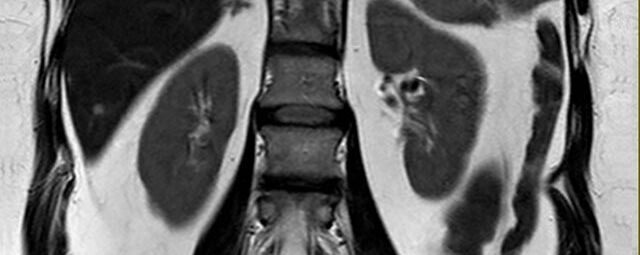

- Nieren

- Abklärung der Ursache einer Harnstauung (MR-Urographie)

- Abgrenzung gutartiger (z.B. Zysten) von bösartigen Nierenerkrankungen (Nierenzellkarzinom)

- Auffälligkeiten an Nebennieren (z.B. Adenom, Karzinom)